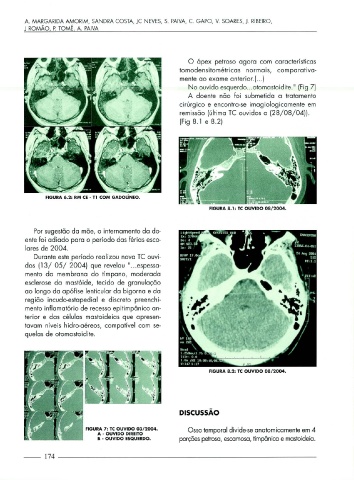

O ápex petroso agora com características

tomodensitométricas normais, comparativa-

mente ao exame anterior.( ... )

N o ouvido esquerdo ... otomastoidite. " (Fig 7)

A doente não foi submetida a tratamento

cirúrgico e encontra-se imagiologicamente em

remissão (última TC ouvidos a (28/ 08/ 04)).

(Fig 8.1 e 8.2)

FIGURA 8.1: TC OUVIDO 08/2004.

FIGURA 8.2: TC OUVIDO 08/2004.